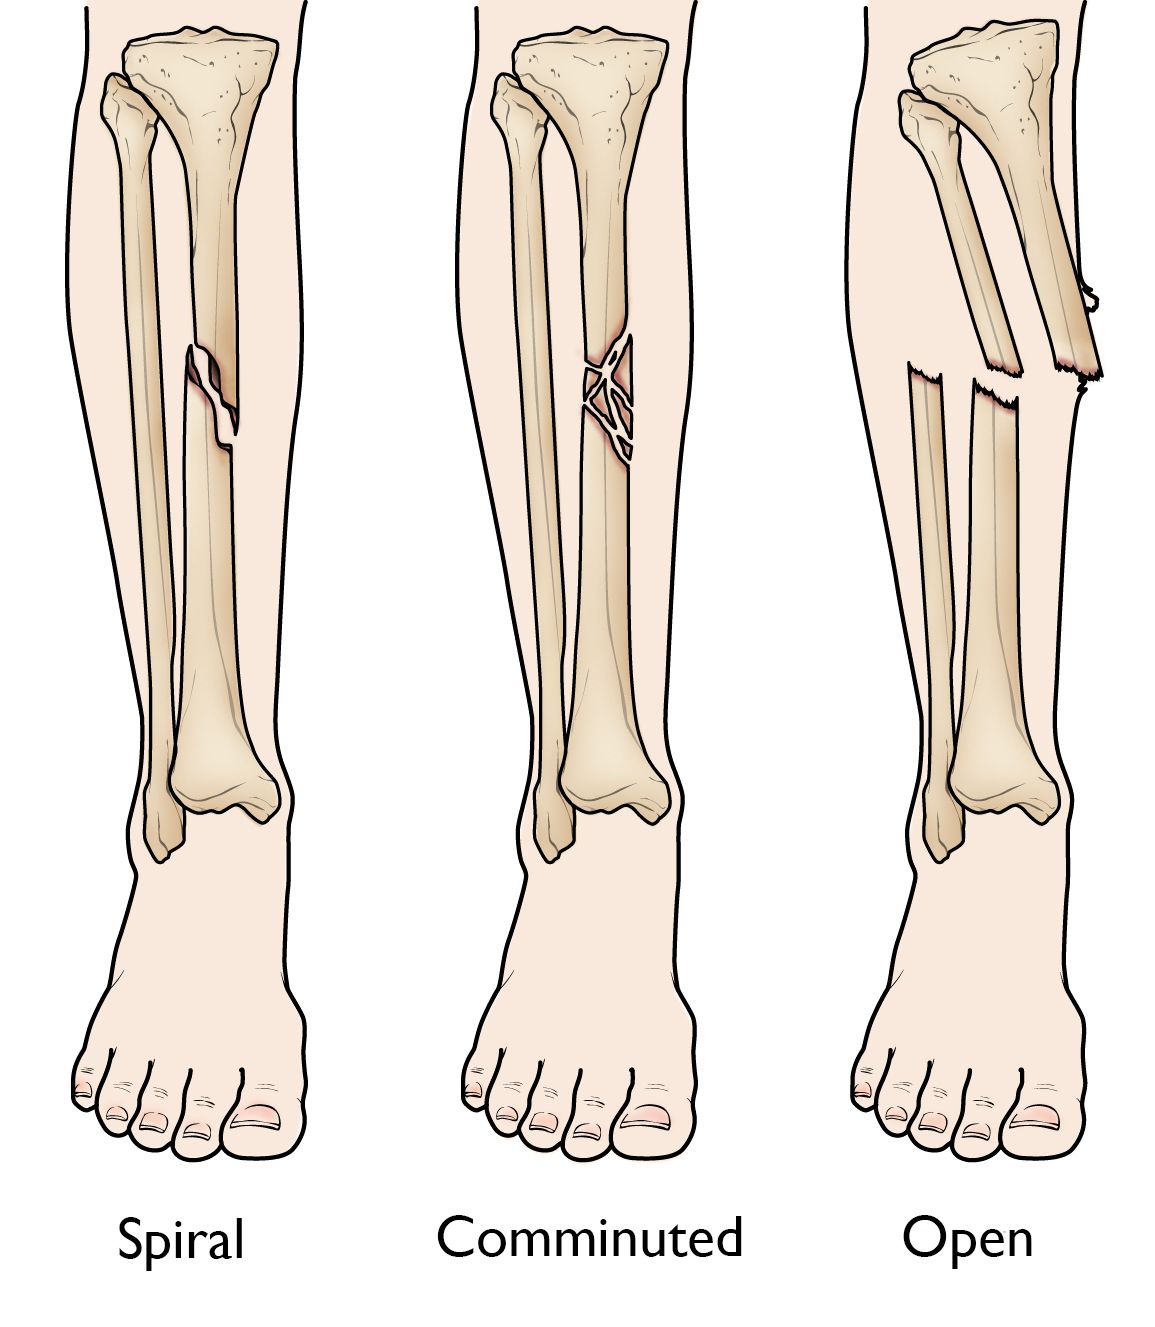

• Spiral fracture: The fracture line encircles the shaft like the stripes on a candy cane. This type of fracture is caused by a twisting force.

• Comminuted fracture: In this type of fracture, the bone breaks into three or more pieces.

• Open fracture: If a bone breaks in such a way that bone fragments stick out through the skin or a wound penetrates (reaches) down to the broken bone, the fracture is called an open or compound fracture. Open fractures often involve much more damage to the surrounding muscles, tendons, and ligaments. They have a higher risk for complications — especially infections — and take a longer time to heal.

Spiral, comminuted, and open tibial shaft fractures

(Left) A spiral fracture encircles the shaft.  (Middle) A comminuted fracture is broken into three or more pieces. (Right) An open fracture breaks through the skin. A transverse fracture pattern is shown here, but an open fracture can occur with any fracture pattern.